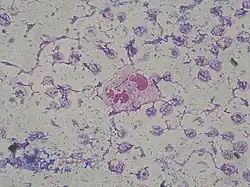

Phagocytosis of P. aeruginosa by neutrophil in patient with bloodstream infection (Gram stain)

Frequently acting as an opportunistic, nosocomial pathogen of immunocompromised individuals, but capable of infecting the immunocompetent, P. aeruginosa typically infects the airway, urinary tract, burns, and wounds, and also causes other blood infections.[41][42]